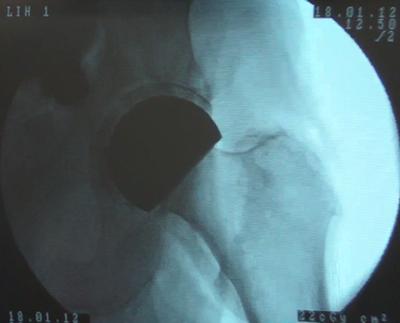

X-ray of the implant

Their work led to the development of two alternative hip replacement systems, the DeltaMotion® cup (or socket) and the DeltaSurf® head (or ball), the first of which is now in clinical use. The team in Southampton also produced a set of computational tools to understand the biomechanical performance of existing implants, and to predict how new design concepts will perform. Furthermore, the partnership produced purpose-designed testing methods for pre-clinical analysis of novel implant concepts, where the innovative designs involved could not be tested in conventional ways.